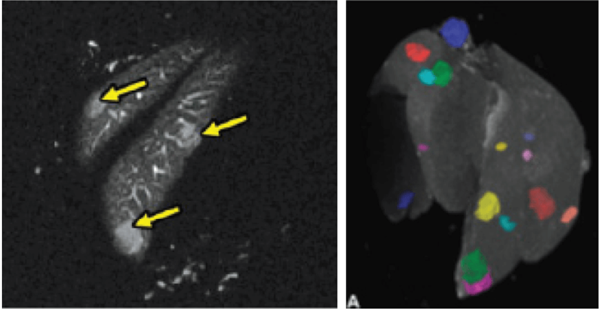

Hindlimb tumor growth: Monitoring the growth of xenograft tumor grown in the mouse hindlimb is identified with T2-weighted images. Segmentation of tumor region of interests (in red) on each tumor-containing slice allows accurate volume quantification. Image Credit: Scintica Instrumentation Inc

Monitoring the growth of xenograft tumor grown in the mouse hindlimb is identified with T2-weighted images. Segmentation of tumor region of interests (in red) on each tumor-containing slice allows accurate volume quantification. Image Credit: Scintica Instrumentation Inc

MRI is a complementary method to bioluminescence imaging in the detection of tumors, allowing a more precise assessment of the location and extent of orthotopic tumors (here, an orthotopic model of prostate bone marrow metastasis). Image Credit: Scintica Instrumentation Inc